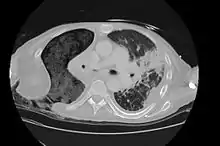

The Eloesser flap is a surgical procedure developed by Dr. Leo Eloesser in 1935 at the San Francisco General Hospital.[1] It was originally intended to aid with drainage of tuberculous empyemas, since at the time there were no effective medications to treat tuberculosis. The procedure was used extensively[2] until the development of effective chemotherapy for tuberculosis in the late 1940s and early 1950s.[3] It is still used occasionally for chronic empyemas.[4][5]

The Eloesser flap is still utilized for patients with chronic empyemas who have not improved despite being treated with antibiotics and first line surgical procedures to remove pus and re-expand the lung such as decortication or video-assisted thoracoscopic surgery.[4] Often they are thought to be too ill for more definitive procedures such as a major thoracotomy or muscle flap transposition.[5] In a recent case series, the most common reasons to need an Eloesser flap were parapneumonic effusions and postresection empyemas, with only 9% done for tuberculosis.[4]